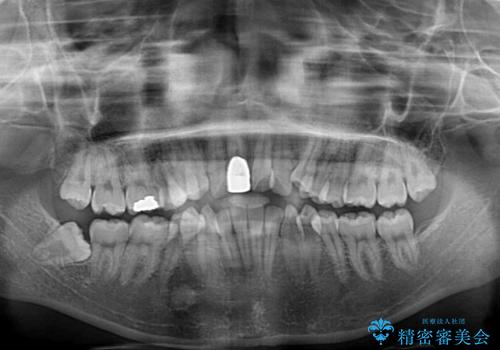

- 八重歯や前歯のデコボコを気にして来院された患者様です。

歯列が前方に傾斜しており、デコボコが強かったため、上下左右第一小臼歯4歯を抜去し、ワイヤー装置による矯正治療を行うこととしました。

上下の正中がずれていましたが、抜歯矯正であったので、極力正中位置を合わせるように治療を進めて行きました。

顎間ゴムの使用などにより、正中位置を改善することができました。